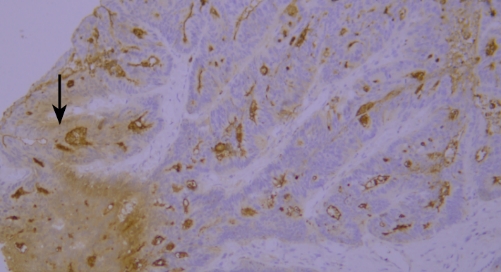

Typical example: CEA staining of paraffin-embedded human colon cancer tissue sections showed accumulation of staining solution (indicated by black arrows).

Recommendation for Resolution: Sufficient washing should be ensured during the experiment to avoid abnormal results caused by residual staining solution.